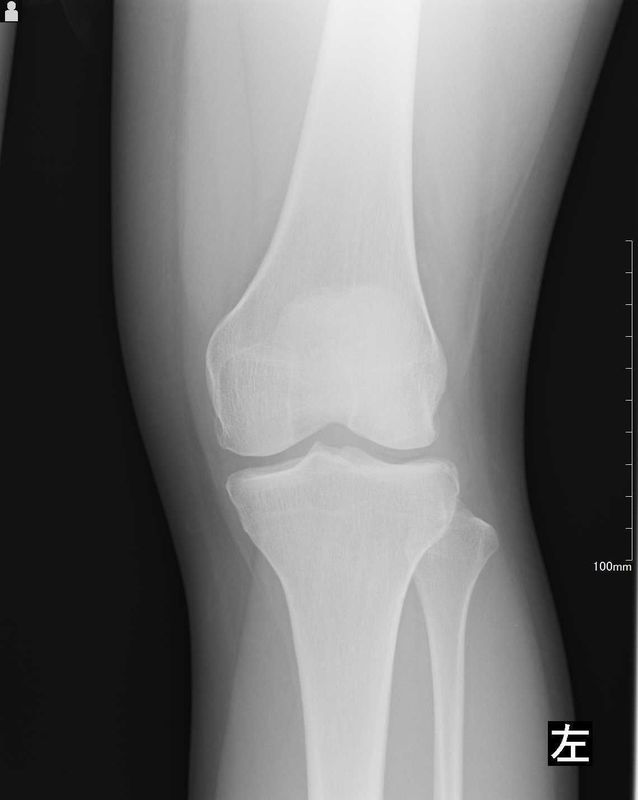

レントゲン所見

| 手術前 | 手術後 |

![]() ![]() | ![]() ![]() |

| 明らかな変形などの病変なし | 術後の変形などはなく術前と変化なし |